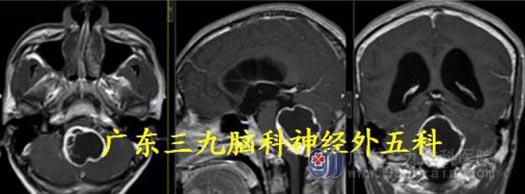

术后MR:小脑蚓部、四脑室病灶彻底切除。术后病理:血管母细胞瘤WHO I 级